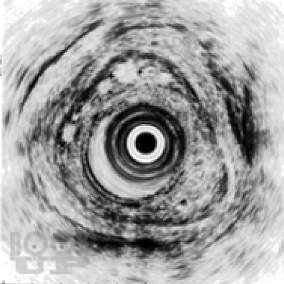

В книге изложены основные сведения по анатомии и патофизиологии пищевода и кардии, освещены вопросы клиники, диагностики, консервативного и оперативного лечения их хирургических заболеваний. С учетом последних достижений медицинской науки и практики описаны нервно-мышечные заболевания пищевода, гастроэзофагеальная рефлюксная болезнь, злокачественные новообразования, травмы, ожоги, болезни оперированного пищевода. Особое внимание уделено хирургической тактике и технике оперативных  вмешательств.